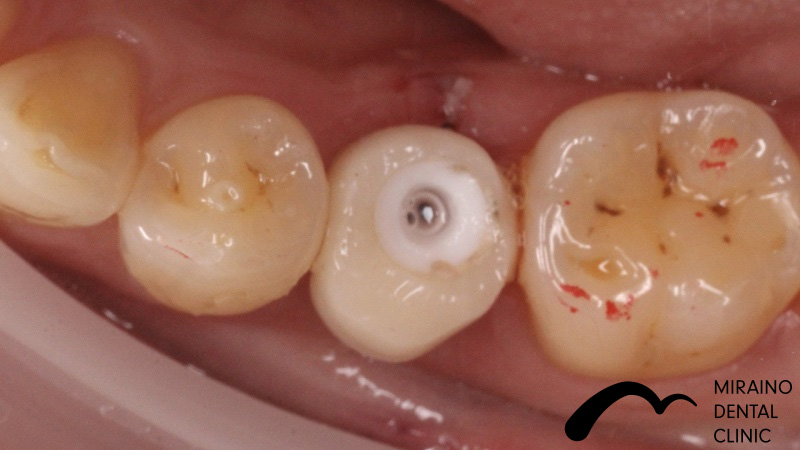

インプラントの症例

Case1

| 施術名 | インプラント |

| 施術の概要 | 10年前ほどに根の先に膿ができて抜歯。 前医では骨が少なくなってしまってインプラントは不可能ということで当院来院。 インプラントOPE時に仮歯まで作成し見た目の回復まで行いました。 その後OPE後3ヶ月で最終の被せ物装着する。 |

クリックして詳細を表示

| 施術の内容 | インプラントは、従来の入れ歯やブリッジとは違い、天然の歯と同じような強くて、美しい歯を取り戻す治療法です。 失った歯の代わりに人工の歯根を埋め込み、その上に人工の歯を装着。 健康な歯を削ることなく、新しい歯が蘇ります。 2~3か月後に上部構造(歯の部分)を装着してかみ合わせを回復させます。 |

|---|---|

| 1歯あたりの治療費 | 450,000円(10年保証込) 骨が薄く造成が必要な場合は追加費用がかかります。 骨造成:30,000円~100,000円 |